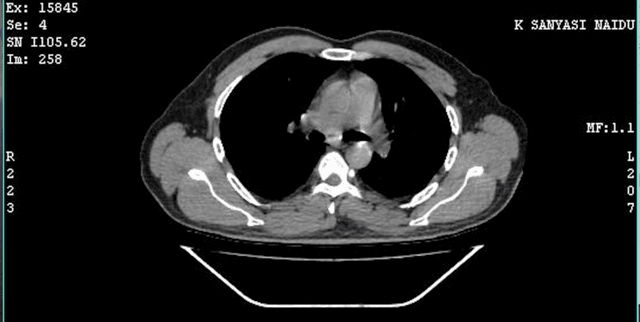

Focuses on diagnostic medical imaging data derived from Computed Tomography (CT or CAT scans), which are medical imaging tests used to generate multiple internal images of the body. This collection provides metadata related to DICOM images captured from 20 subjects. The data is significant for research into precise diagnostics, specifically for identifying Cardiomegaly, as it includes labels for 11 subjects identified with the condition and 9 healthy subjects. This resource supports the analysis of medical imagery for targeted health conditions.

The data scope is limited to 20 anonymised subjects. The collection effort involved institutions such as Lincoln University College and Omega Hospitals. The subjects are categorised into two groups: those with Cardiomegaly and those who are healthy. Specific details regarding the geographic origin, exact age demographics, or the timeline of data capture are not provided.